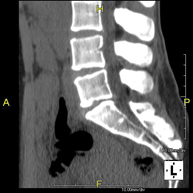

Prova radiològica que consisteix en obtenir imatges de les vèrtebres dorsals d'alta definició anatòmica, mitjançant l'ús d'un equip de TC (Tomografia Computaritzada). Indicacions: dolor dorsal, estudi de desviacions de la columna, traumatisme. - TC Columna lumbar

Prova radiològica que consisteix en obtenir imatges de les vèrtebres lumbars d'alta definició anatòmica, mitjançant l'ús d'un equip de TC (Tomografia Computaritzada). Indicacions: dolor lumbar sense / amb irradiació a les cames, dificultat per caminar, traumatisme. - TC de sacre-còccix